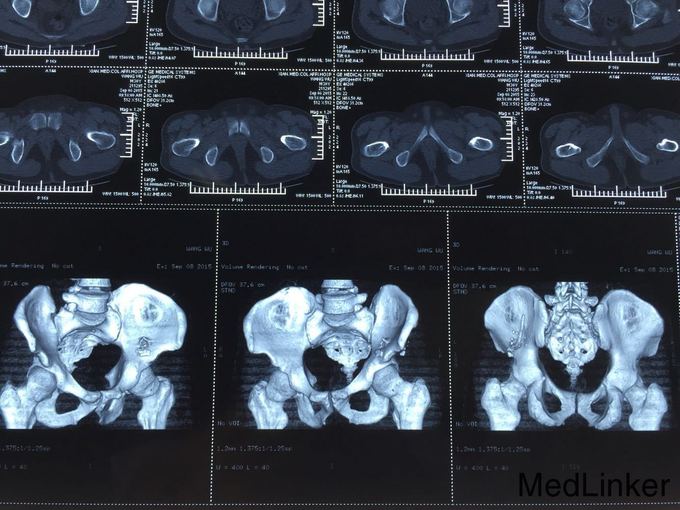

查体:T:36.6℃,P:80次/分,R:19次/分,Bp:130/85mmHg。心肺未见明显异常,腹平坦,无腹壁静脉曲张,腹部柔软,无压痛、反跳痛,腹部无包块,左侧腰髂部近左臀部可见钢筋样异物刺入直达左下腹腹壁皮下,未穿透腹壁皮肤,左臀部皮肤裂伤伴出血,伤口处压痛,肝脾肋下未触及,左下腹压痛,Murphy氏征阴性,移动性浊音阴性,肝脾肾区无叩击痛,肠鸣音未见异常。 辅助检查:全腹部CT检查示:1.盆腔见条状金属致密物,从左臀穿向前下腹部皮下,长约28cm;2.左侧腹膜周围见少许渗出性改变;3.左侧精索肿胀,其内气体影,左侧睾丸肿胀;4.左侧髂骨骨折。

诊断: 左侧腰骶部开放性损伤:左侧腰髂部盲管伤,腹膜后血肿,左侧精索静脉损伤,左侧髂骨骨折。 诊疗过程:入院后积极完善术前检查,无绝对手术禁忌,予以急诊行剖腹探查手术:左下腹乙状结肠外侧部位可见腹膜后血肿形成,初步判断钢筋样异物经左侧骶髂关节部位刺入至左下腹腹膜后部位后再经由壁腹膜外位至左下腹壁,遂决定行腹膜后血肿探查清除手术:于乙状结肠外侧后腹膜血肿部位打开后腹膜并清除积血,探查见左侧髂血管未见外伤性改变,探查见左侧精索静脉断裂伴出血,予以细线结扎,左侧输尿管、左肾、膀胱未见外伤性改变。冲洗腹腔干净,继续探查判断左下腹钢筋样异物均位于腹膜外位且未伤及重要器官,遂经腹壁侧予以拔出,查腹腔无活动性出血,,于左下腹腔术区置橡皮引流管一条经左侧腹壁引出,逐层缝合关闭腹腔,随后行臀部外伤扩创术。术后患者恢复佳,顺利出院。